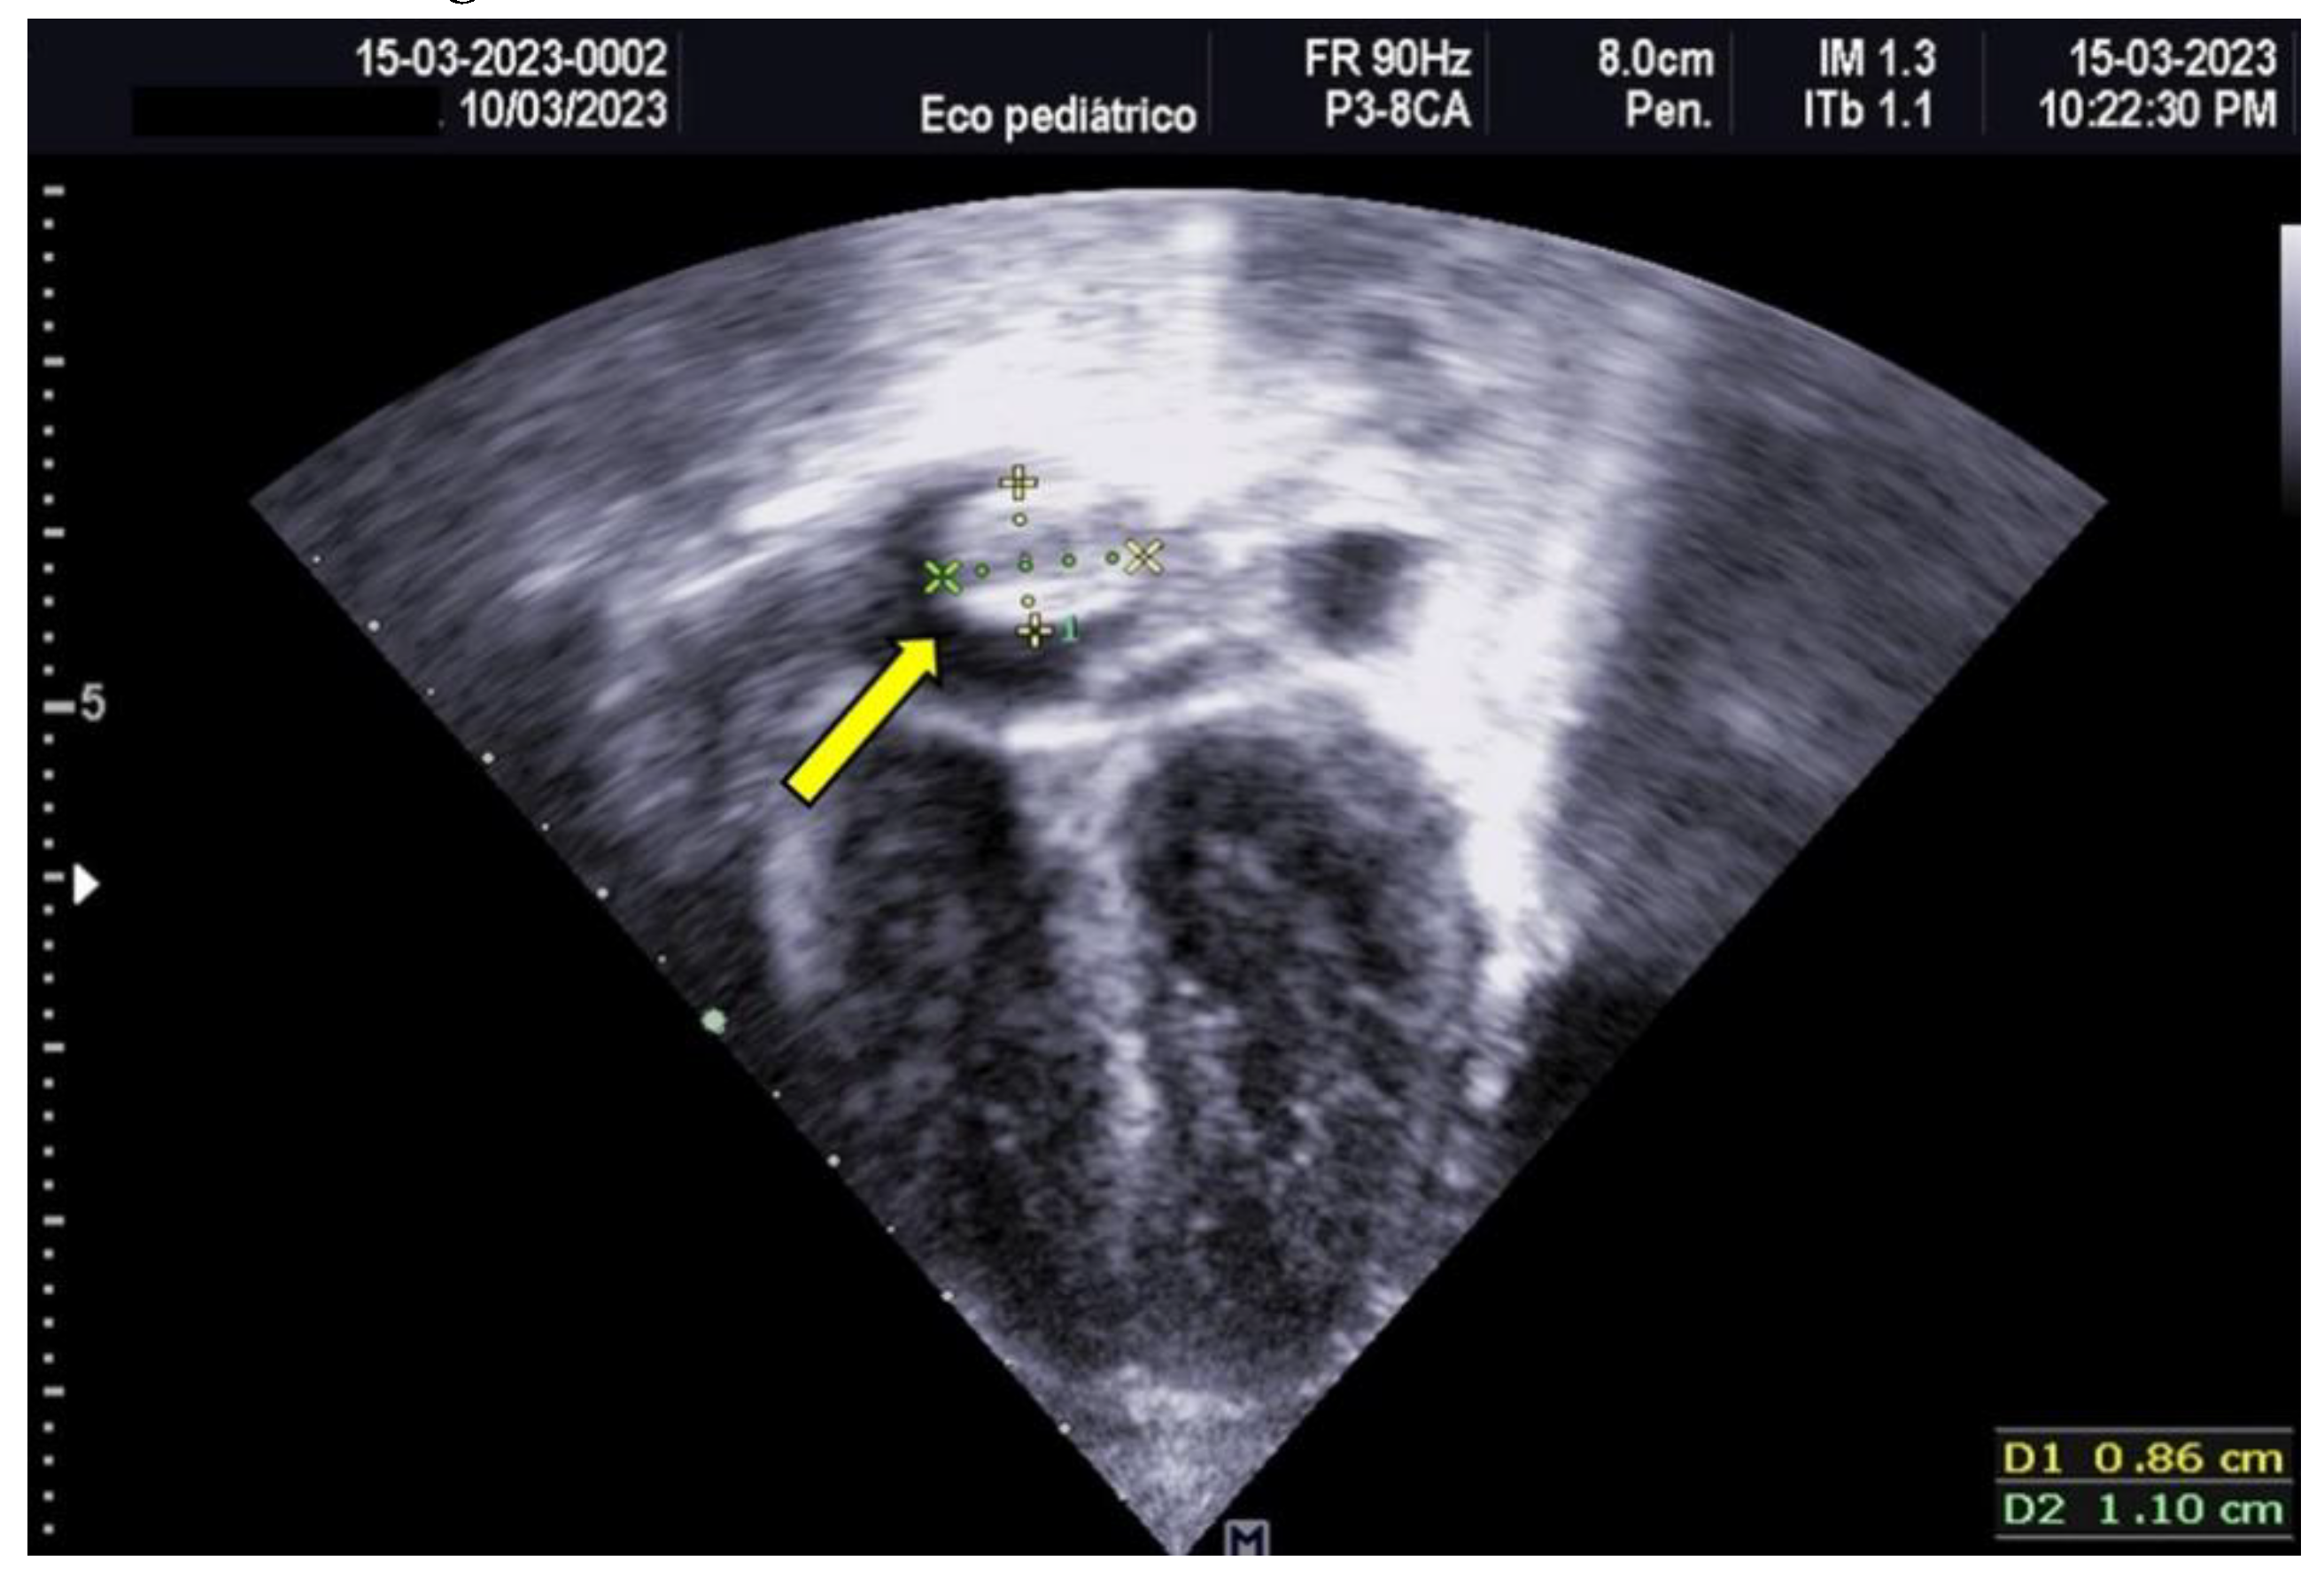

The neonate was referred to Hospital General de Cancún due to tachypnea. Oxygen therapy was initiated using a headbox, and a 5 Fr umbilical catheter was inserted without complications. A pediatric cardiology evaluation, prompted by the maternal history of gestational diabetes, revealed asymmetrical septal hypertrophy and a non-obstructive thrombus (measuring 0.94 × 0.83 cm) in the right atrium (as shown in Figure 1).

Figure 1. Transthoracic Echocardiogram, Apical 4-Chamber View Hyperechoic image corresponding to a thrombus measuring 1.1 x 0.86 cm, attached to the roof of the right atrium.